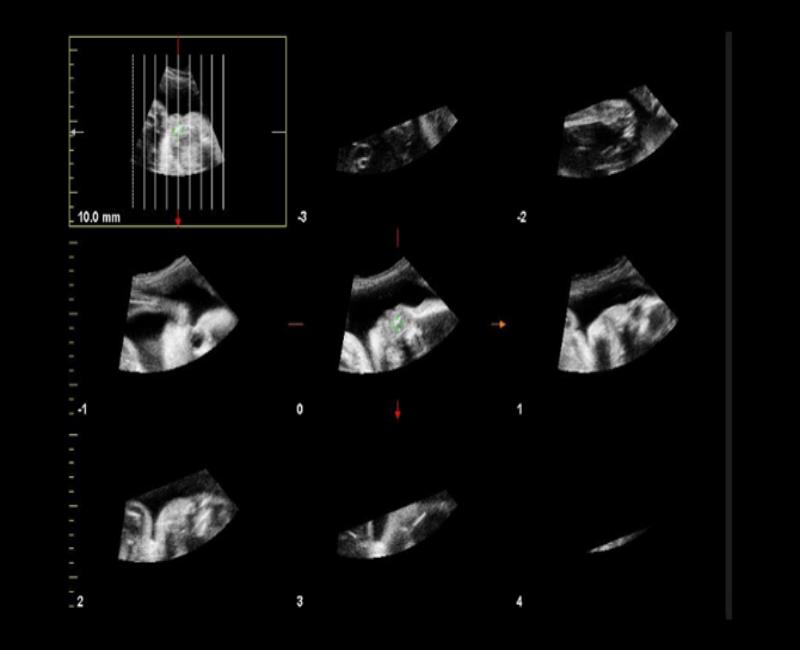

TMI - Siêu âm đa lát cắt.

may sieu am mylab x6

TSI - dựng 3D/4D từ các góc độ hẹp.